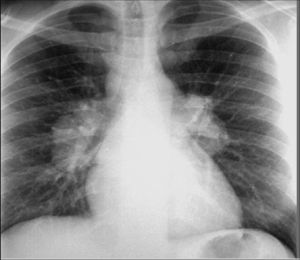

1.2 X線檢查:異常的胸部X線表現常是結節病的首要發現,約有90%以上患者伴有胸片的改變。目前普通X線片對結節病的分期仍未統一。1961年,Scandding將結節病分為四期(1~4期),近年又將其分為五期(0,1~4期)。而目前較為常用的仍是Siltzbach分期,國內亦採用此分類方法。

123 Ⅱ期 肺門淋巴結腫大,伴肺浸潤。肺部病變廣泛對稱地分布於兩側,呈1~3mm的結節狀、點狀或絮狀陰影。少數病例可分布在一側肺或某些肺段。病灶可在一年逐漸吸收,或發展成肺間質纖維化,約占25%。